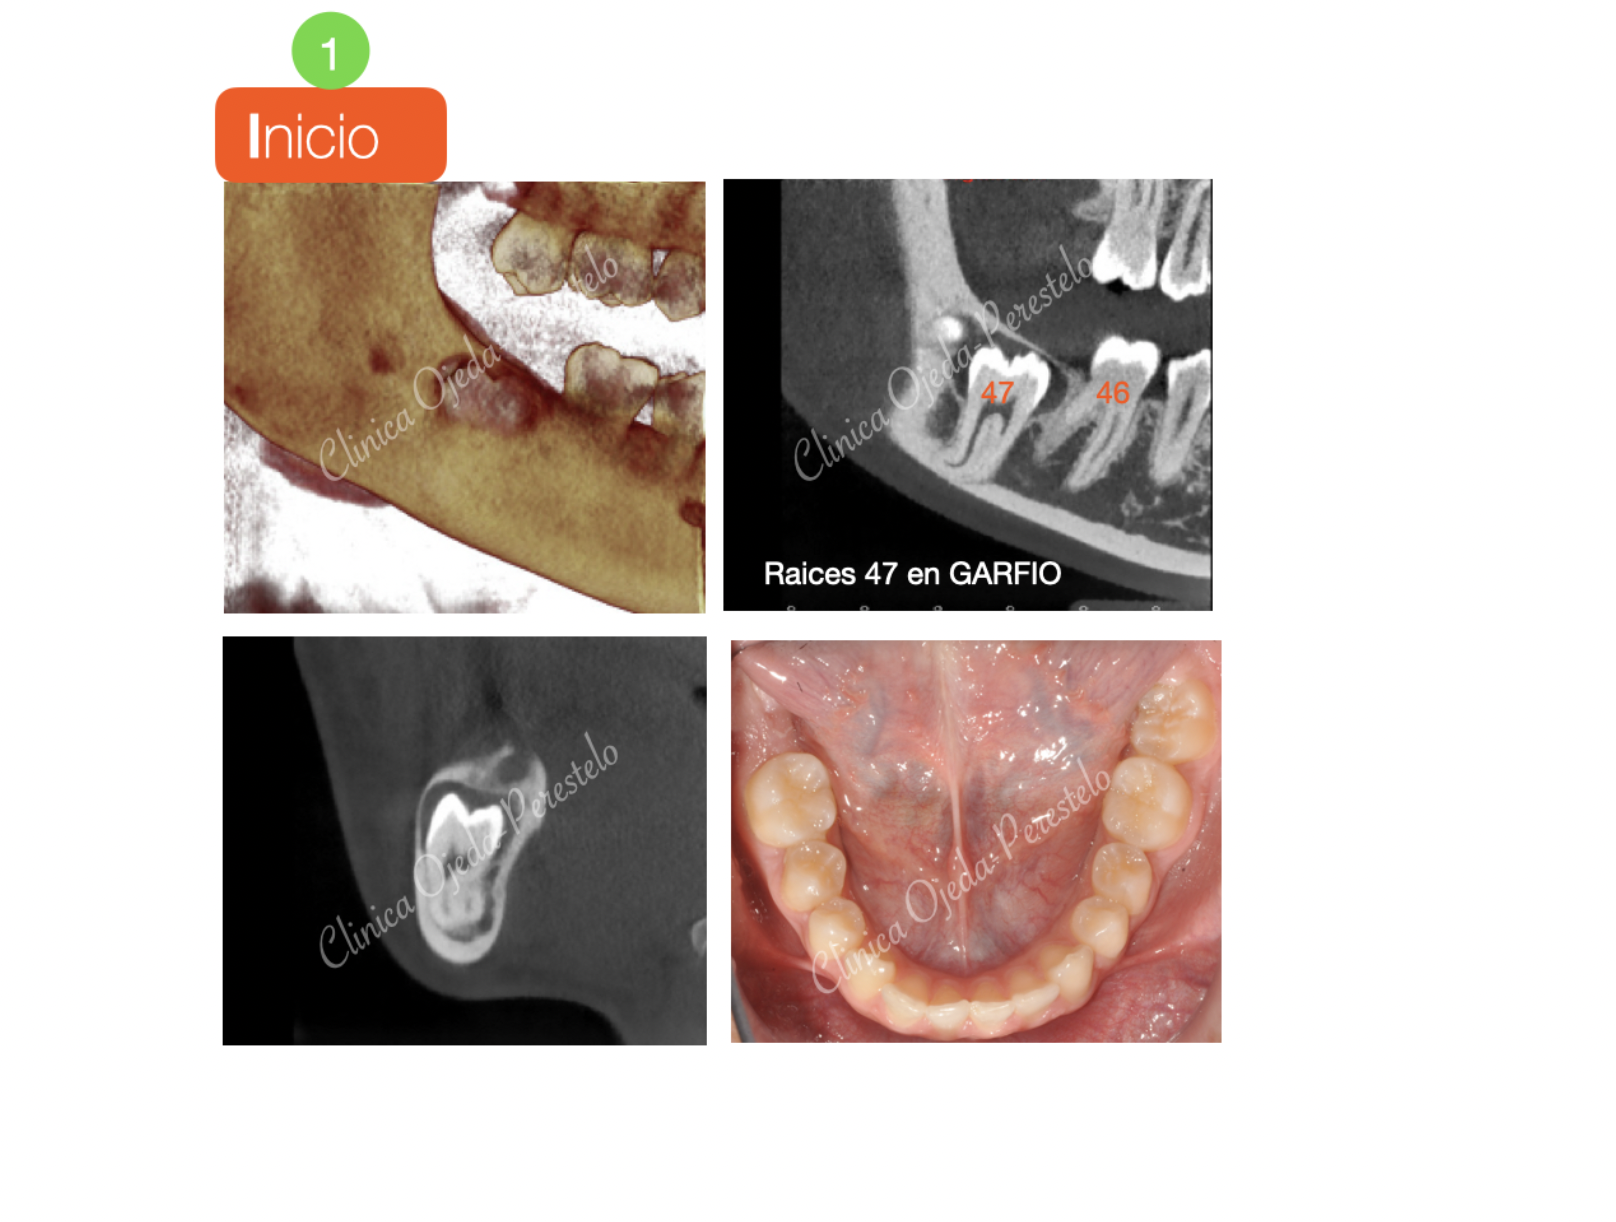

2ºMolar Mandibular Retenido

Presentamos el caso de una paciente con un 47 retenido a nivel del borde mandibular con las raíces severamente dilaceradas y preocupada porque su cirujano le ha comentado que en caso de  realizarle la extracción, su mandíbula tiene probabilidades de fracturarse. Nuestro Objetivo es ubicar la pieza 47 en contacto con el 46 y llevarla hasta su plano de oclusión.